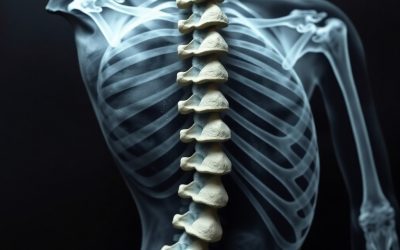

Como eliminar la lumbalgia para siempre: Ejercicio Terapéutico

La lumbalgia es una de las dolencias más comunes en la sociedad actual y que más puede afectar a la calidad de vida, no solo en el rendimiento deportivo, si no enla vida cotidiana. Si buscas la forma de como eliminar la lumbalgia para siempre, aquí descubrirás la...

Lesiones de Espalda: comprende y recupera tu lesión

Las lesiones de espalda representan una de las principales causas de dolor y limitación funcional en la población. Este problema afecta tanto a personas sedentarias como a deportistas y un tratamiento adecuado es esencial para recuperar la movilidad, reducir el dolor...